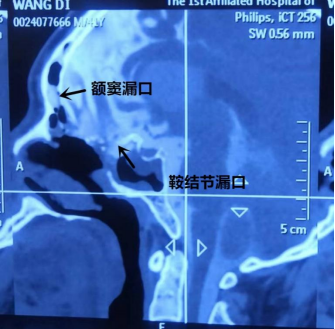

经过系统抗炎治疗10天后,患者意识清楚,脑脊液白细胞降到70x106/L。经CT室孙重阳医生会诊确定患者既往手术脑脊液漏口愈合良好,本次脑脊液漏口两个,分别位于右侧鞍结节和右侧的额窦后壁。

术前脑池造影结果:漏口分别在右侧鞍结节和右侧额窦